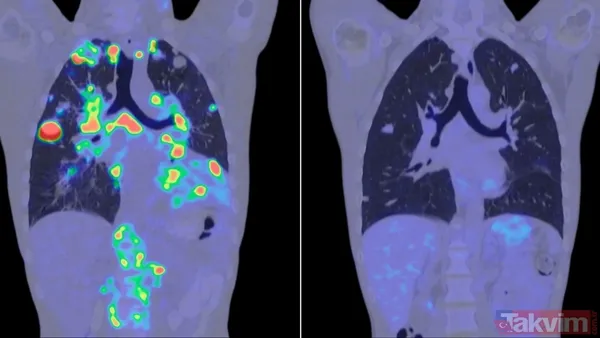

-En sık görülen kanser türleri arasında meme, akciğer, rahim ağzı, prostat ve kan kanserleri yer alırken uzmanlar erken teşhis ve düzenli taramaların hastalığın seyri üzerinde belirleyici rol oynadığını vurguluyor.